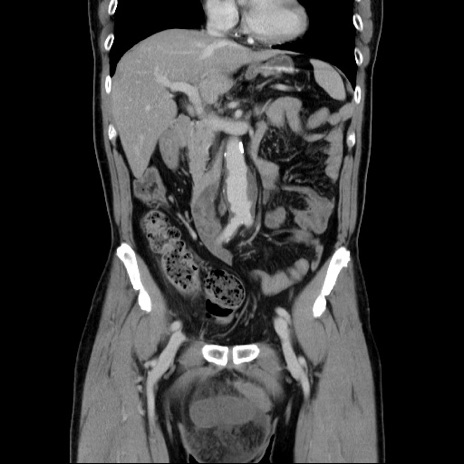

症例34(冠状断像)

【症例】60歳代 男性

【主訴】右鼠径部膨隆

【現病歴】1年程前より右鼠径部膨隆あり。自己にて還納可能だったため放置していた。3時間前より右鼠径部の脱出を認め、還納困難となり受診。

【既往歴】高血圧

【身体所見】右鼠径部に小児頭大の膨隆あり。弾性硬であり、用手還納は困難。左鼠径部にも膨隆を認める。脱出はなし。